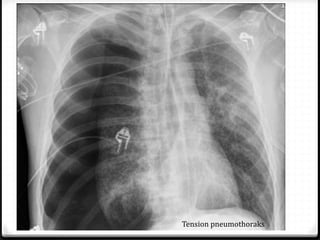

Tension pneumothoraks

Pneumothoraks

0 Udara pada rongga pleura

0 15%–40% ditemukan pada trauma thoraks

0 Ruptur alveoli karena ada tekanan meninggi secara tiba-tiba

pada intrathorakal akibat trauma dengan atau tanpa fraktur

costae

0 Radigrafi polos >>

0 ± 10% tidak dapat dievaluasi dengan radiografi polos  CT scan